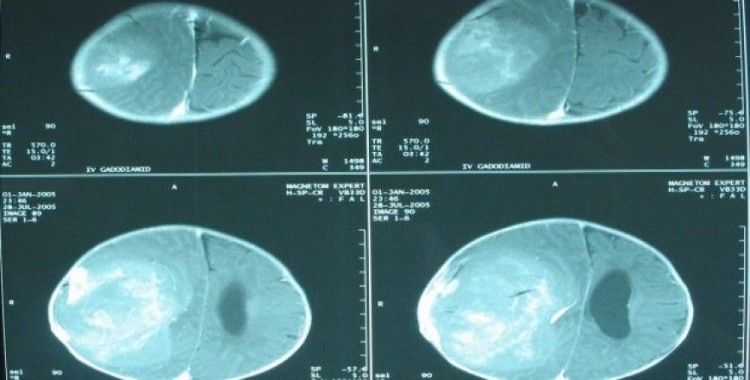

Vasküler cerrahi menenjiom glial tümör lomber disk hernisi bel fıtığı bel sırt boyun ağrıları tanı ve tedavisi boyun fitiği cerrahisi mikrodiskektomi bel fıtığı tedavisi beyin pili beyin tümörleri ameliyatı kafa travmaları mikro cerrahi subdural hemoraji periferik sinir hastalıkları beyinde damar tıkanıklığı genel beyin cerrahisi. Gönül aslan cv türkçe.